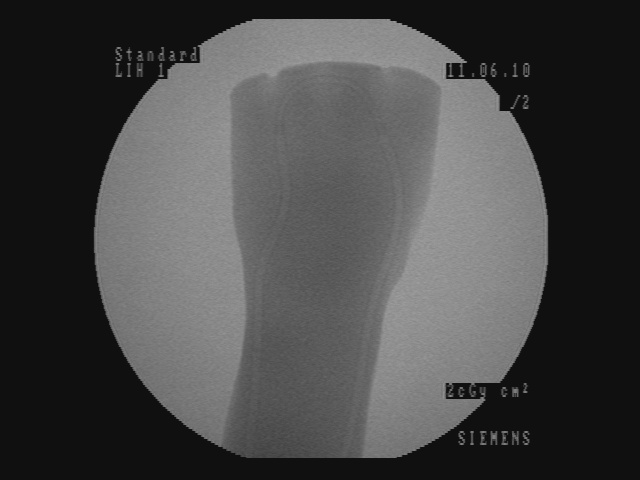

2.3 Visualization results

In Figure 5, for each scenario, one selected image Ilayerssubscript𝐼𝑙𝑎𝑦𝑒𝑟𝑠I_{layers} in the sequence can observed with different values of α𝛼\alpha, β𝛽\beta, γ𝛾\gamma and δ𝛿\delta. Each row i𝑖i corresponds to the sequence i𝑖i. From left to right, the layer visualized in Ilayerssubscript𝐼𝑙𝑎𝑦𝑒𝑟𝑠I_{layers} is getting closer to the X-ray source viewpoint. In the column (a), the furthest layer (the X-ray image) is displayed. In the column (b), the second layer (the background), in the column (c), the blending of the front layer with the background, in the column (d), the blending of the three layers and finally, in the column (e), the closest layer is shown. Additional images from the sequences can be visualized in the supplementary video where interaction between the layers by changing the blending values can be observed.

Despite the fact that the background cannot be ideally recovered, a manual post processing step involving inpainting is applied and displayed in the column (f) of Figure 5. We believe that the multi-layer visualization concept is an interesting and profound solution offering numerous possibilities in the surgical areas, as well as, the mixed reality communities.

(a) (α,β,γ,δ)=(0,0,1,1)𝛼𝛽𝛾𝛿0011(\alpha,\beta,\gamma,\delta)=(0,0,1,1)

Refer to caption

(b) (α,β,γ,δ)=(0,1,0,0)𝛼𝛽𝛾𝛿0100(\alpha,\beta,\gamma,\delta)=(0,1,0,0)

(c) (α,β,γ,δ)=(0.4,0.6,0,0)𝛼𝛽𝛾𝛿0.40.600(\alpha,\beta,\gamma,\delta)=(0.4,0.6,0,0)

(d) (α,β,γ,δ)=(0.2,0.3,0.5,0.5)𝛼𝛽𝛾𝛿0.20.30.50.5(\alpha,\beta,\gamma,\delta)=(0.2,0.3,0.5,0.5)

(e) (α,β,γ,δ)=(1,0,0,0)𝛼𝛽𝛾𝛿1000(\alpha,\beta,\gamma,\delta)=(1,0,0,0)

(f) Inpainting

Figure 5: Per row i𝑖i, multi-layer image Ilayerssubscript𝐼𝑙𝑎𝑦𝑒𝑟𝑠I_{layers} of one selected frame in the sequence i𝑖i with different blending parameters (α,β,γ,δ)𝛼𝛽𝛾𝛿(\alpha,\beta,\gamma,\delta)

Similar to results from Habert et al. [6], the images resulting from synthesization are not as sharp as a real video image. The area synthesized by our algorithm is approximately 20 cm ×\times 20 cm (C-arm detector size), which is small compared to the wide-angle field of view from the Kinect v2. Reduced to the area of synthesization, the video and depth from Kinect is not of high resolution enough for sharper results. More specialized hardware with smaller field of view and higher resolution RGBD data would solve this problem. Moreover, several artifacts can be seen around the hand and surgical instruments in the synthesized image due to high difference and noise in depth in the RGBD data from the 2 cameras. However, our results demonstrate that our method is working well, since the incision line and cross drawn on the hand model and patient hand are perfectly visible in the recovered background image and can be seen in transparency through the hands and surgical tools in the images of Figure 5-column (c) and (d). In the scalpel sequence (sequence 6) in Figure 5-column (b), it can be seen that the tip of the scalpel is considered as background, this is due to the margin of few centimeters used for background segmentation. In this image, the scalpel is actually touching the skin.